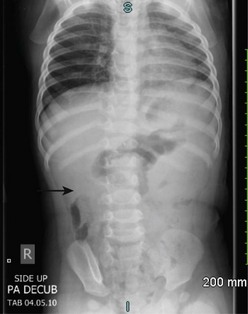

In half of cases, the diagnosis of intussusception can be suspected on plain flat and upright abdominal radiographs (Fig. 38-3). Suggestive radiographic abnormalities include an abdominal mass, abnormal distribution of gas and fecal contents, sparse large bowel gas, and air-fluid levels in the presence of bowel obstruction. However, plain films have limited value in confirming the diagnosis and are not used as the sole diagnostic test. They are best utilized as a screening tool when one of the abnormal findings listed above is found.19